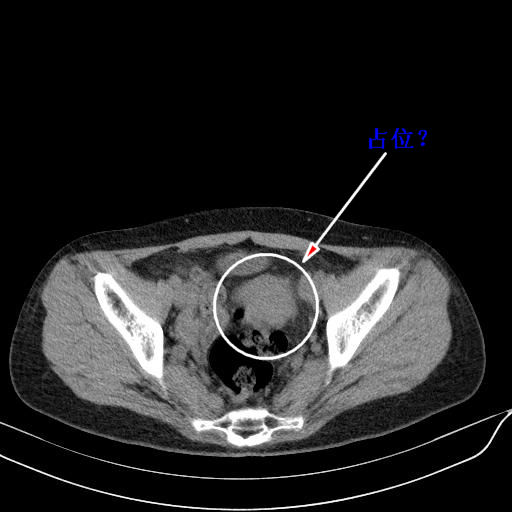

标题: CT23965:无外伤史,下腹痛 [打印本页]

标题: CT23965:无外伤史,下腹痛

肠道未准备,继续往下扫,乙状结肠占位不排除。建议钡灌或结肠镜检查。

好像有肿瘤。

乙状结肠占位不排除

肠道肿瘤,建议行钡剂灌肠检查。